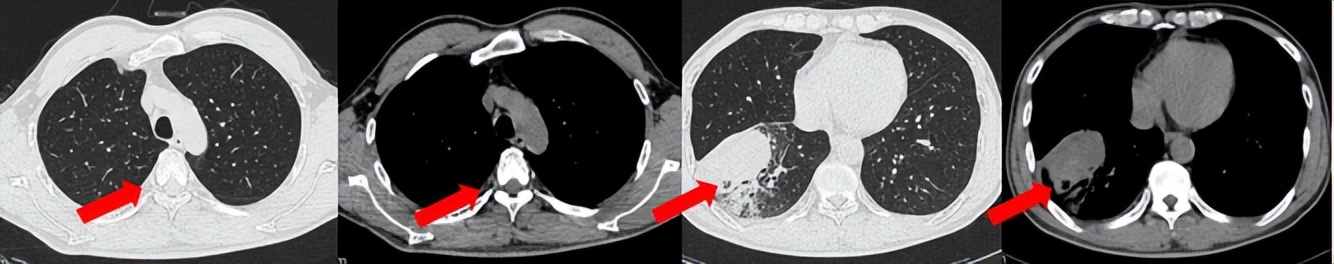

治疗经过:2024.08开始口服赛普替尼(160mg,bid)。2024.09复查胸CT评效PR。2025.1复查胸CT:右肺下叶外基底段见一不规则形实性肿块,大小约94mm×87mm,边缘呈分叶状,其内密度不匀。右侧胸腔见少许水样密度影。评效PD,PFS=5个月。患者未同意再次组织活检,目前应用卡博替尼治疗,仍在随访中。治疗期间未出现毒性反应。

2024.08

2024.09评效PR

2025.01评效PD

治疗经过:2025.01开始口服普拉替尼(400mg,qd)。2025.03复查胸CT:左肺上叶、右肺上叶、左肺斜裂见多发实性结节影,长径范围约3-17mm,较大者大小约17mm×12mm,位于左肺上叶下舌段,可见分叶、毛刺、胸膜凹陷、棘状突起征象。纵隔内小淋巴结。评效PR,随访中。治疗期间未出现毒性反应。

2024.12

2025.03评效PR